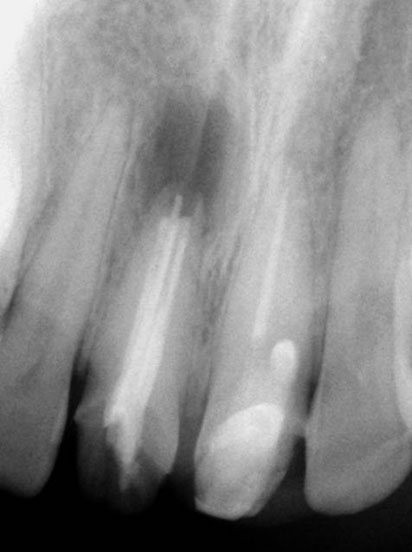

Pre-op

Residual caries seen after temp removal.

After caries removal

Cotton pellets placed over the palatal and Disto-buccal orifices to prevent the instrument from slipping into those canals.

Fractured instrument in mesio-buccal canal

Fractured instrument removed with ultrasonics

Canals cleaned, shaped and obturated

Fiberglass-post and composite core placed

Post-op